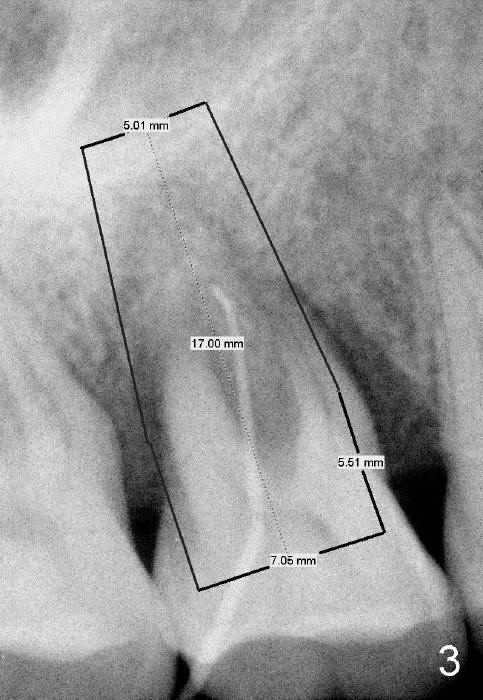

The tooth #3 has severe periodontitis with probably endodontic lesion (Fig.1,2). The patient is a 43-year-old man with apprehension of dentistry. An acute infection causes pain and tooth shift (Fig.4,5). A 7x17 mm immediate implant is planned (Fig.3). The palatal socket is shallow (Fig.6 P), corresponding to severe recessive palatal root (Fig.5 P). The osteotomy is created mainly in the buccal socket (Fig.6 B), exactly in the lingual slope of the septum. Initially osteotomes are used, followed by tap placement (Fig.7 T (4.5x20 mm at the depth of 17 mm). When the implant is placed as planned (Fig.8 I), there is more vertical contact (Fig.8 red line) than that associated with the tap (Fig.7 red line). The corresponding insertion torque is between 50 and 60 Ncm. There is only one small gap buccally, which is filled with bone graft (Fig.9 <). After the insertion of a short abutments with vertical slots (Fig.9,10 A), perio dressing is used to cover the wound. The palatal socket is expected to heal uneventfully (Fig.10 P). In fact, it does in 7 days (Fig.12 P); the bone graft in the mesiobuccal aspect is healing and stabilized (Fig.11 <). By two weeks postop, the mesiobuccal socket has healed (Fig.13 <). With removal of a diseased tooth, our body has amazing power to heal.